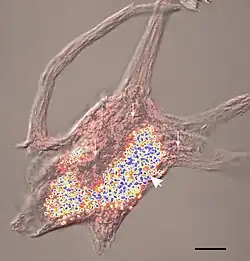

Lipofuscin is the name given to fine yellow-brown pigment granules composed of lipid-containing residues of lysosomal digestion.[1][2] It is considered to be one of the aging or "wear-and-tear" pigments, found in the liver, kidney, heart muscle, retina, adrenals, nerve cells, and ganglion cells.[3]

Lipofuscin quantification is used for age determination in various crustaceans such as lobsters and spiny lobsters.[26][27] Since these animals lack bony parts, they cannot be aged in the same way as bony fish, in which annual increments in the ear-bones or otoliths are commonly used. Age determination of fish and shellfish is a fundamental step in generating basic biological data such as growth curves, and is needed for many stock assessment methods. Several studies have indicated that quantifying the amount of lipofuscin present in the eye-stalks of various crustaceans can give an index of their age. This method has not yet been widely applied in fisheries management mainly due to problems in relating lipofuscin levels in wild-caught animals with accumulation curves derived from aquarium-reared animals.